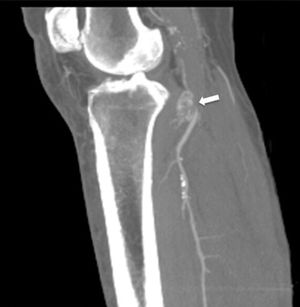

Figure 4.

Eco-Doppler: bypass control. (A) Superficial pathway of the in situ SVG. (B) Permeable bypass (arrow head). Femoral condyle (asterisk).

A male, 67 years of age, obese, with high blood pressure and dyslipidemia presented at the emergency department due to pain, cold and functional impairment of his lower left limb of 24-h onset. During anamnesis, the patient stated he had had a chronic intermittent pain in his left knee for a long time. A previous simple knee X-ray showed an osteochondroma (Fig. 1). The patient presented with a femoral pulse but with no popliteal and distal pulses. Artery examination was normal in the contralateral extremity. A CT angiogram was requested for the lower limbs which showed thrombosis of the popliteal artery adjacent to the osteochondroma (Figs. 2 and 3). We decided to perform in situ revascularization with femoro-popliteal saphenous vein graft (Fig. 4) avoiding the tunneling technique for anatomical positioning. To date, after 3 years of follow-up with eco-Doppler, the bypass continues maintaining permeability with ankle-arm index of 0.9, and no signs of popliteal vein injury.